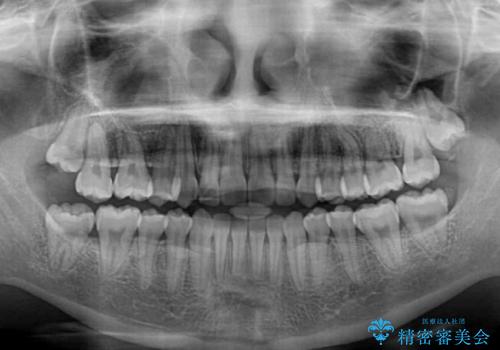

- 八重歯を気にして来院された患者様です。

本来であれば八重歯の隣後方の歯を抜歯するのですが、その後ろの歯が乳歯であり後続永久歯もなかったため、乳歯を抜去することとしました。

前から5番目の乳歯は、後続永久歯である小臼歯と比べて幅径が大きいため、移動に時間がかかりましたが、きれいに仕上げることができました。